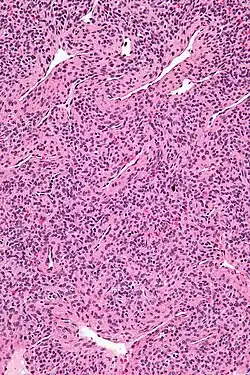

Micrograph of a myopericytoma. H&E stain.

Myopericytoma is a rare perivascular soft tissue tumour. It is usually benign and typically in the distal extremities.[1]